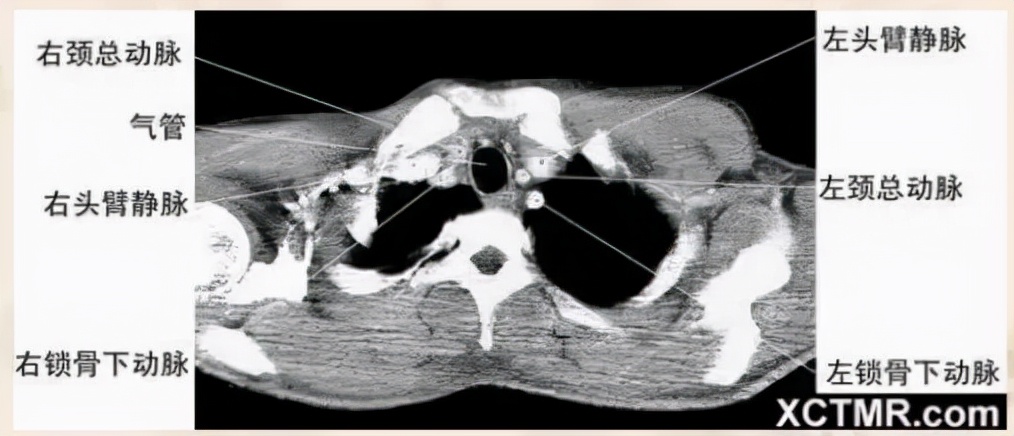

主动脉弓上层面